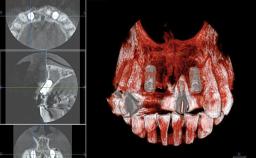

Replacement of Two Central Incisors with Non-Splinted Crowns on Bone-Level Implants

A 27-year-old female patient was referred to the Clinic of Oral Surgery and Stomatology of the University of Bern due to acute pain in the region of her two maxillary central incisors. The patient was in good general health. She reported a bicycle accident approximately 5 years earlier in which teeth 11 and 21 had been traumatized but neither fractured nor displaced. Several weeks after the accident, endodontic treatment was performed on both central incisors, although the patient did not recall the precise reasons for this decision. About 2 years ago, non-vital bleaching had been conducted, in accordance with the “walking-bleach” principle, due to progressive discoloration of teeth 11 and 21.